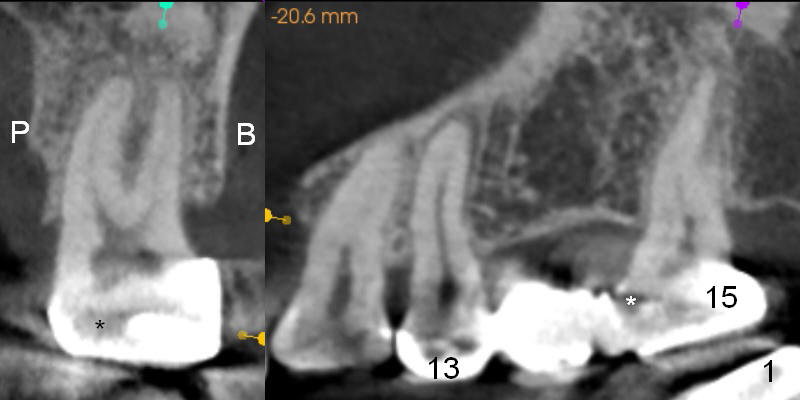

A 47-year-old woman complains of chewing pain at #15 after #30,31 implant placement.  It appears that there is mesial open margin (caries, Fig.1).  The bridge is to be sectioned at the junction between #13 and 14 (Fig.2 red line).  It is expected that #14 and 15 units will fall out by themselves.  Examine and remove caries at #15.  Conduct pulpal test and start RCT if there is time and necessity.  There is one common buccal orifice with two canals (Fig.2 arrowheads).  Be prepared for provisional for #15.  An implant will be placed at #14.